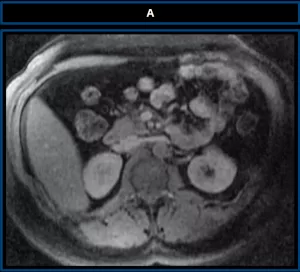

Coronal T1-weighted post-contrast MRI (A) shows a well-defined mass at the base of the left hemithorax with imaging features identical to native liver, including signal intensity and enhancement pattern — supporting the diagnosis of hepatic heterotopia. Our case corresponds to Type I a pedunculated accessory lobe herniated into the thoracic cavity through a congenital diaphragmatic defect.